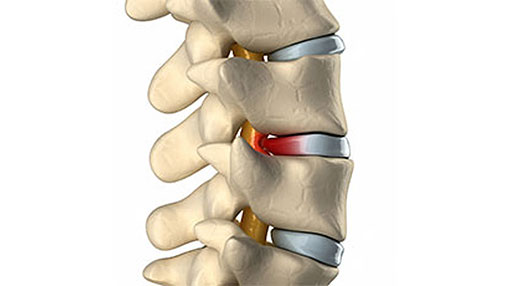

Bone grafting is a surgical procedure in which fractures or cracks in bones are repaired. This is typically done by stabilizing the broken or cracked bone using fixation materials such as surgical screws, plates, wires, or screws. The goal of this procedure is to restore the alignment of the bones and provide the necessary stability to promote proper bone healing.

A bone graft is a surgical procedure used to repair fractures or tears in bones by fixing the damaged bone pieces using plates or surgical screws, usually in the form of a patch on the bone’s surface. Bone grafts help restore bone stability, promote healing, and are used in a variety of cases that require surgical bone fixation, including:

- Bone grafting is used to help stimulate the healing of bones in areas where natural healing is slow or challenging. It can create an optimal environment for fractured or weak bones to recover and heal.

- Bone grafting can enhance the stability of fractured or cracked bones by fixing bone fragments.